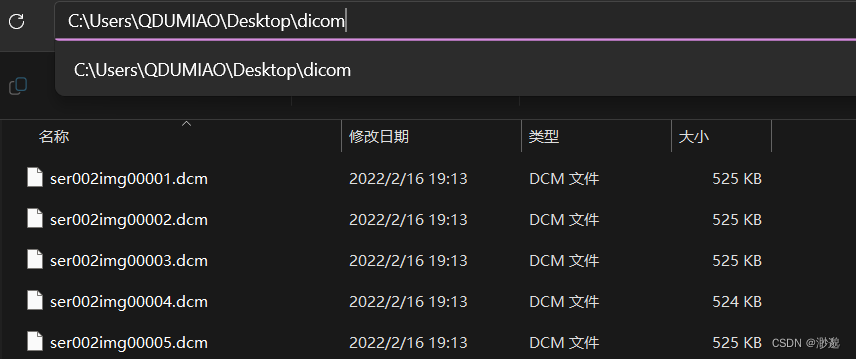

oripath = r'C:\Users\QDUMIAO\Desktop\dicom' #dicom文件夹

dicom文件都应该存放在一个文件夹中

运行代码可以发现dicom文件已经成功被转换为了三种格式。